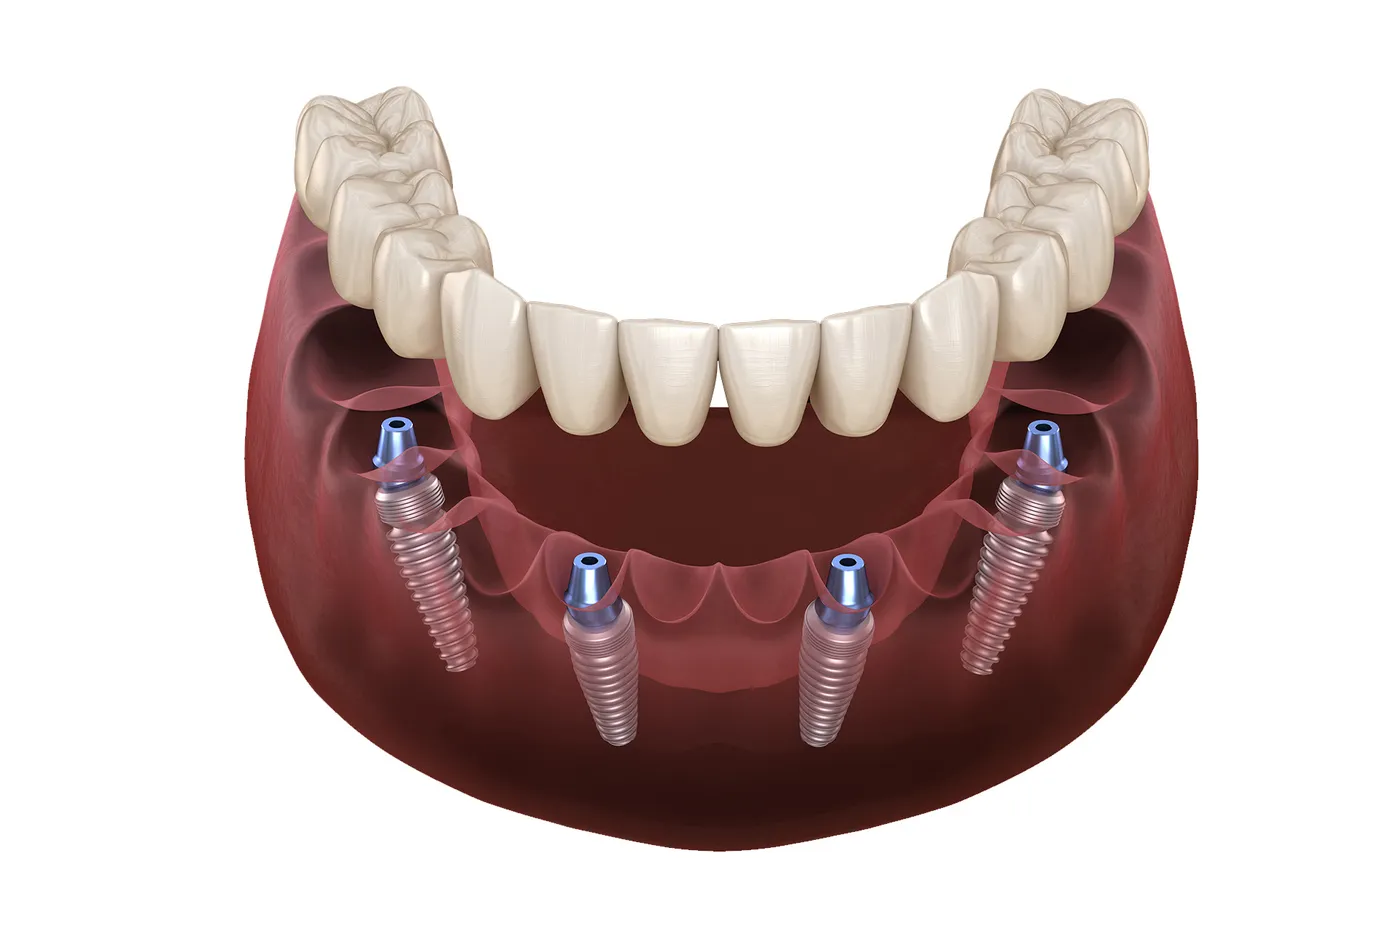

This approach utilizes the full spectrum of available dental therapies, including porcelain crowns, porcelain veneers, implant bridges, All-on-4 implants, ZOOM! teeth whitening, and more. No matter how deteriorated your teeth and gums may be, Dr. Patel has the skills to fully restore your smile.

Dental Implants

Dental implants represent one of the most groundbreaking advancements in dental reconstruction. For years, replacing missing teeth has been a challenge due to the limitations of traditional methods. However, dental implants have revolutionized tooth replacement, offering a solution that is indistinguishable from natural teeth in both appearance and function. Implants are, without a doubt, the superior choice for replacing missing teeth.